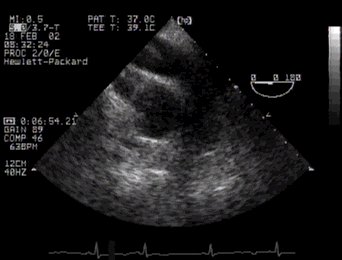

1. Short axis basal (Aortic Valve, RVOT, atrial septum) 'ME AV SAX'

2. The following view is really rather important, mainly because it contains an unmistakable landmark - the 'Mercedes-Benz sign'of the aortic valve in cross section (av). Posterior to this valve (and close to the probe) you can see the left atrium, to the patient's right (your left) is the right atrium, and ventrally is the right ventricular outflow tract.

UP Basal aortic valve CLICK FOR VIDEO: aortic valve (basal)

Note that the anatomical section is slightly off-true, so the sign is skewed - a useful tip! Note that in this fairly cephalad view, the interatrial septum is thick - more inferiorly it thins markedly. The right ventricular outflow tract is also well seen (rvot).